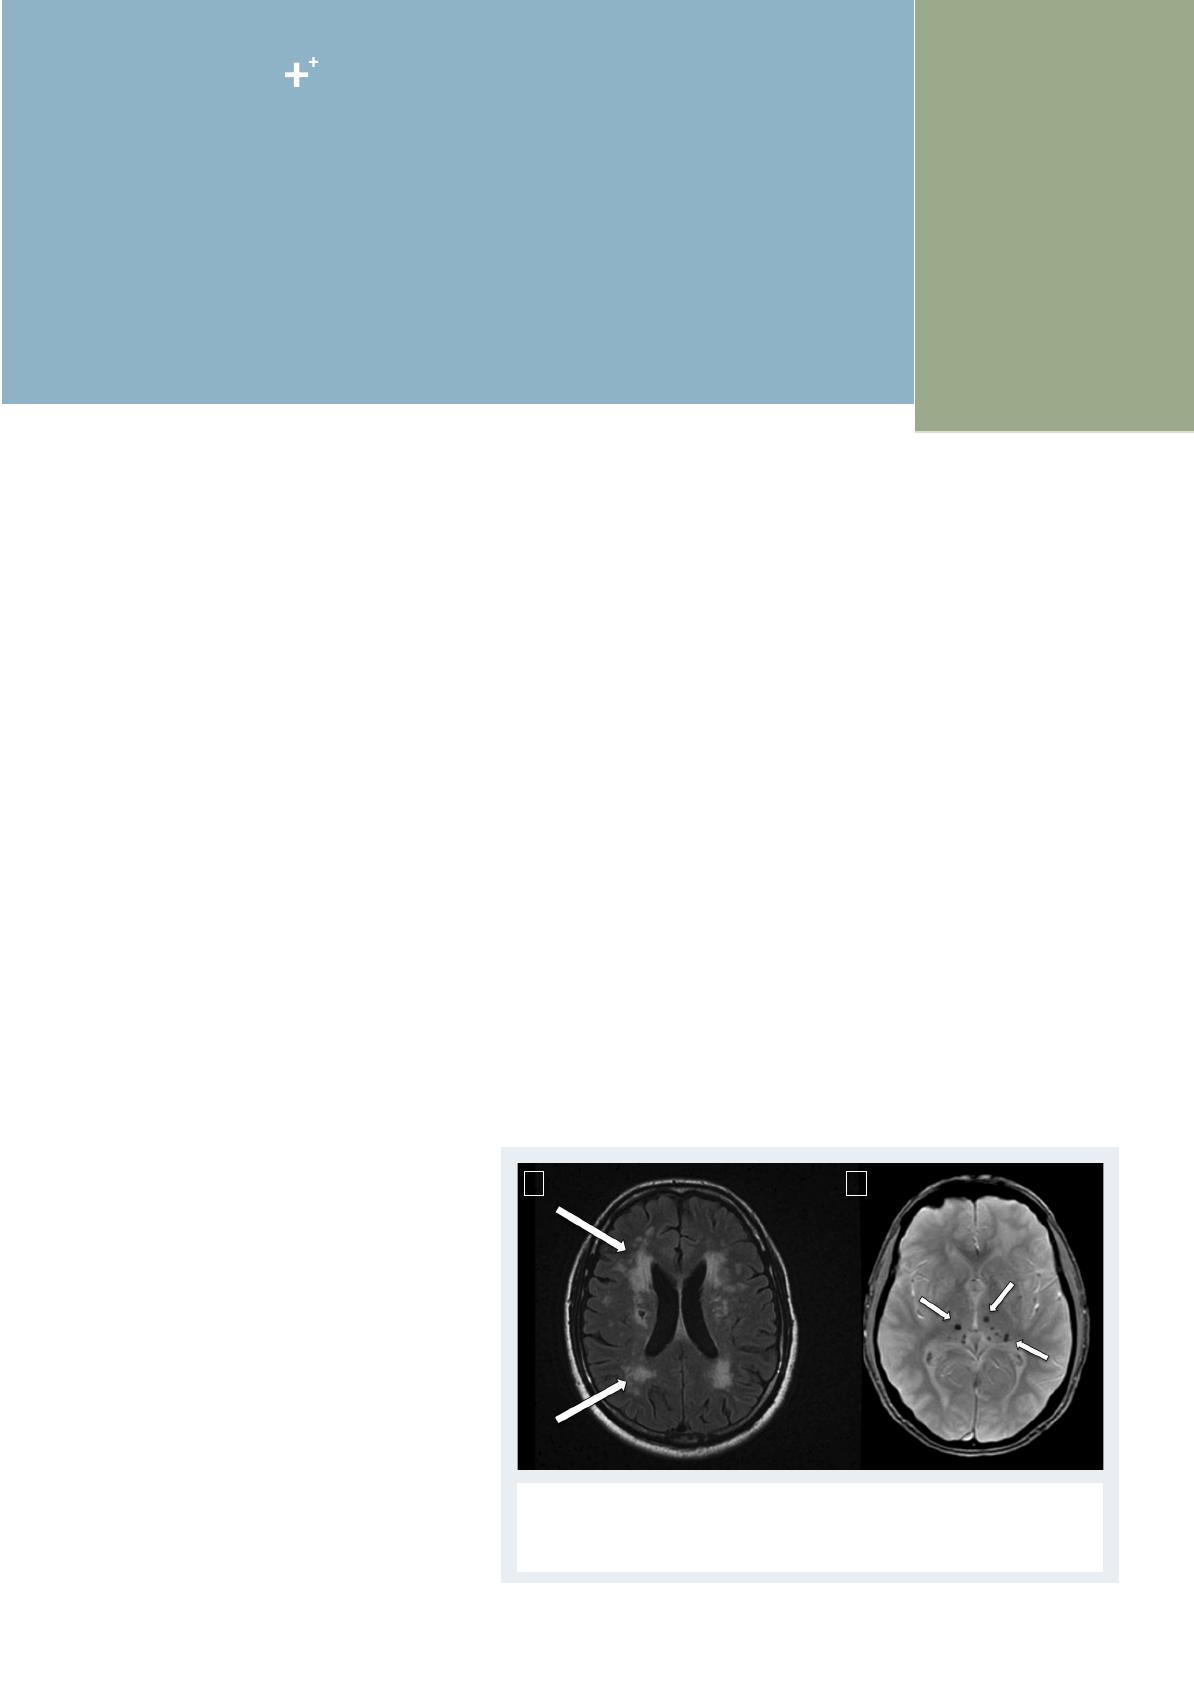

L’indication d’une anticoagulation efficace – c’est-

à-dire curative – par héparine non fractionnée ou

héparine de bas poids moléculaire en phase aiguë de

l’IC reste exceptionnelle à cause du risque de trans-

formation hémorragique cérébrale (ou plus rarement

d’hémorragie systémique) lié à ce traitement. Toutes

les études à l’heure actuelle ne montrent aucun

bénéfice du traitement anticoagulant en phase aiguë

de l’IC. Le bénéfice de ce traitement, en particulier

chez les patients qui présentent une FA, reste contre-

balancé par l’augmentation du risque d’hémorragies

intracérébrales symptomatiques (figure 2).